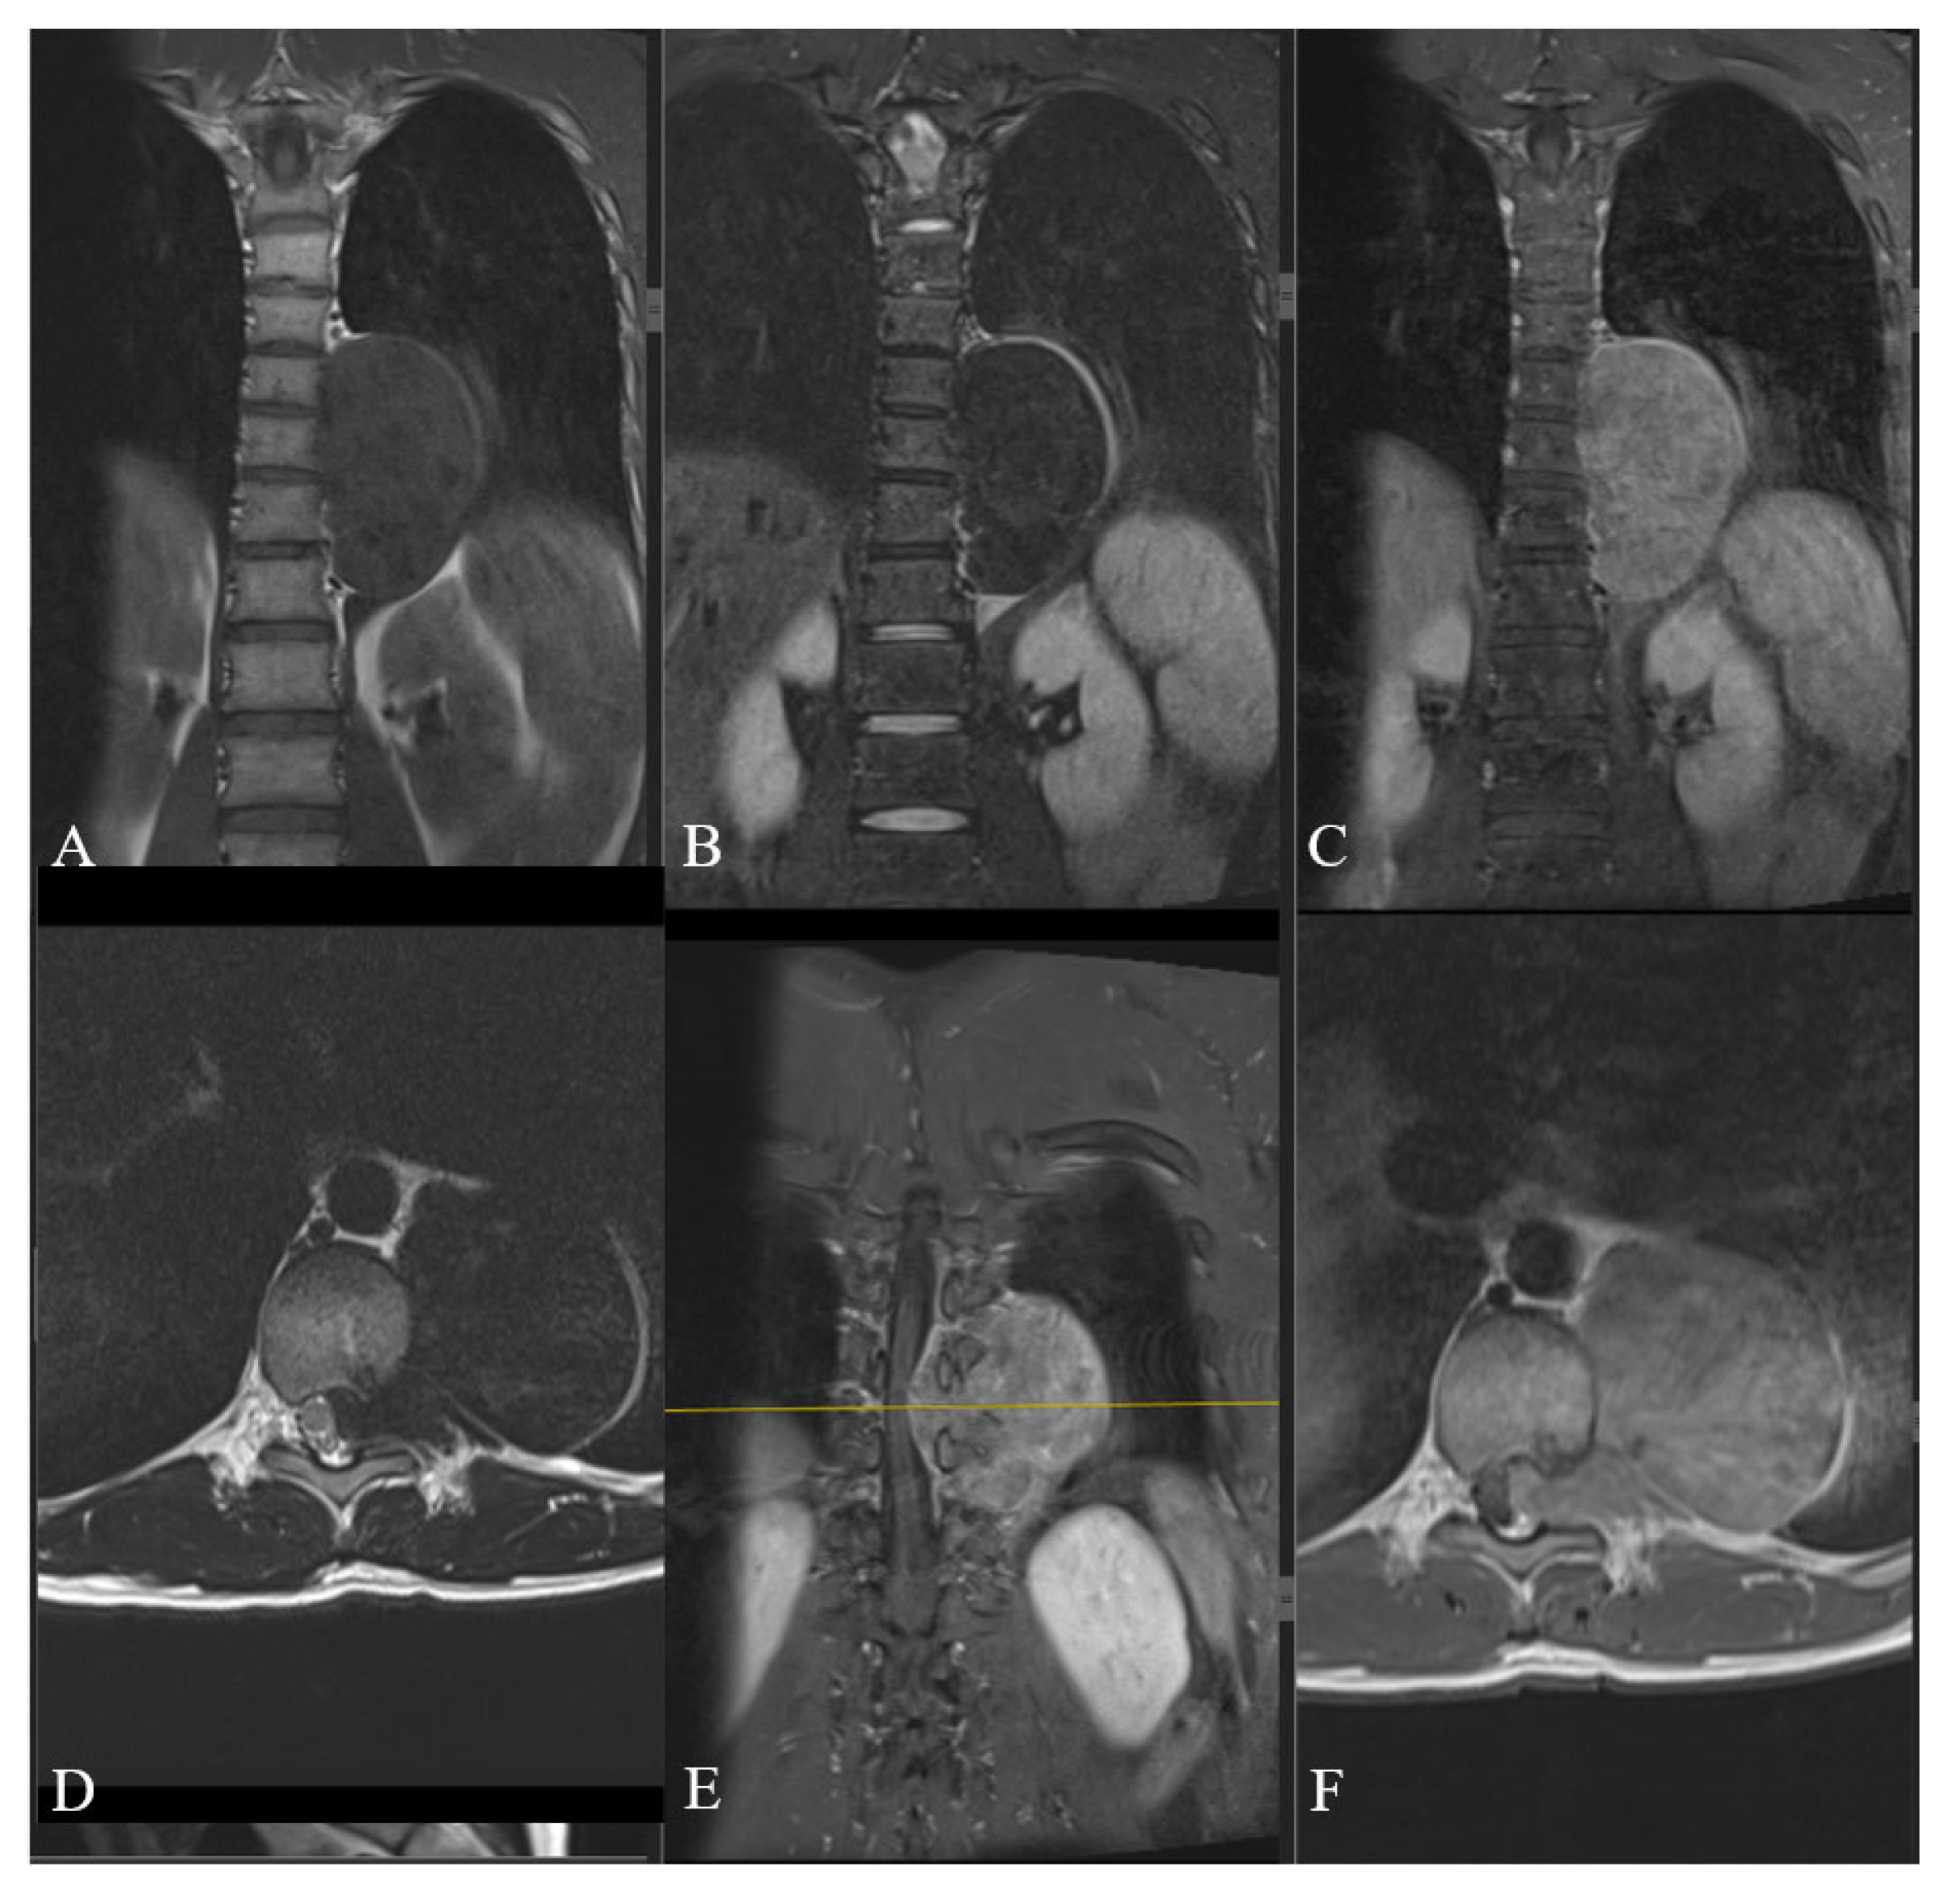

2. Case Report